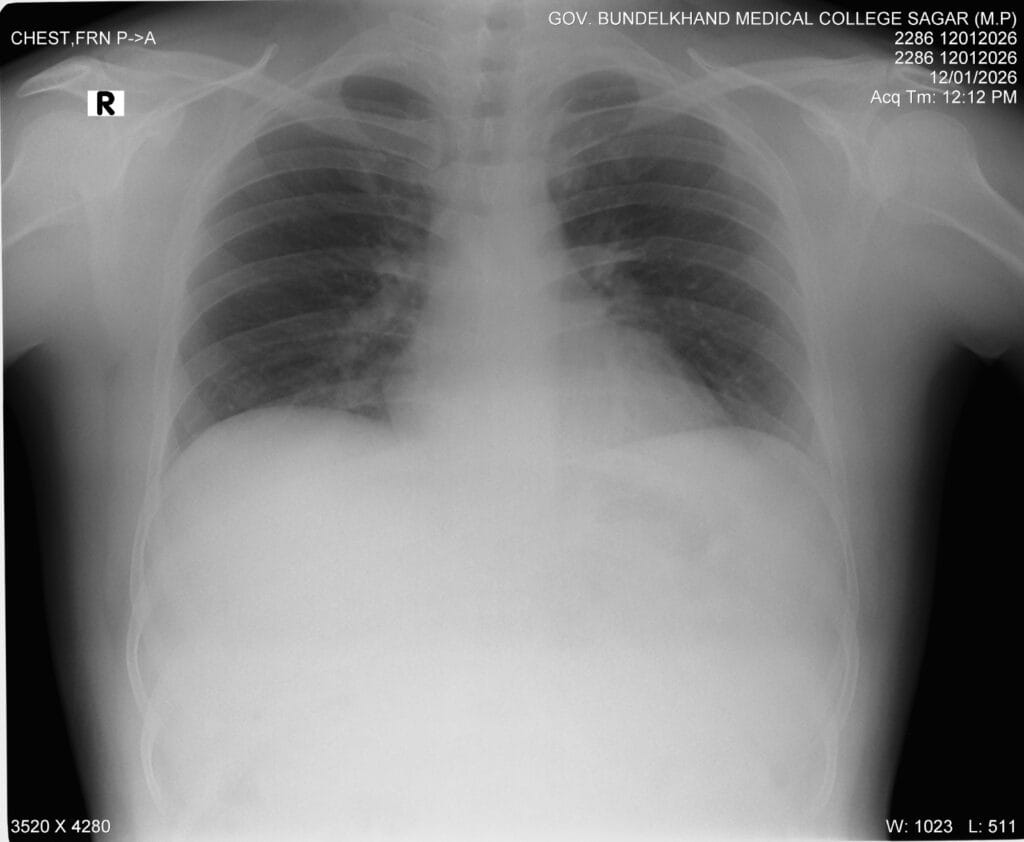

This my chest X ray PA view Read it Guys🙂

Step 5: C – Cardiac

- Assess heart size

- Cardiothoracic ratio < 50% in PA view

- Check cardiac borders

Loss of borders may indicate adjacent lung pathology (silhouette sign).

Step 6: D – Diaphragm

- Right hemidiaphragm is normally slightly higher

- Costophrenic angles should be sharp

- Look for free gas under diaphragm

Step 4: B – Breathing (Lung Fields)

Always compare both lungs side by side.

- Blunting of costophrenic angles